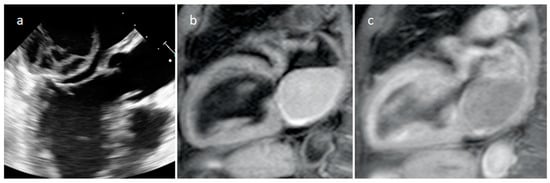

3.4. Pericardial Cyst

| Pericardial cyst | Adulthood | Right pericardiophrenic angle | Asymptomatic | Fluid-filled, thin-walled, homogeneous, no internal enhancement | Low echodensity | Hypodense well-defined lesion with a wall | Hypo T1w, hyper T2w, no internal enhancement |